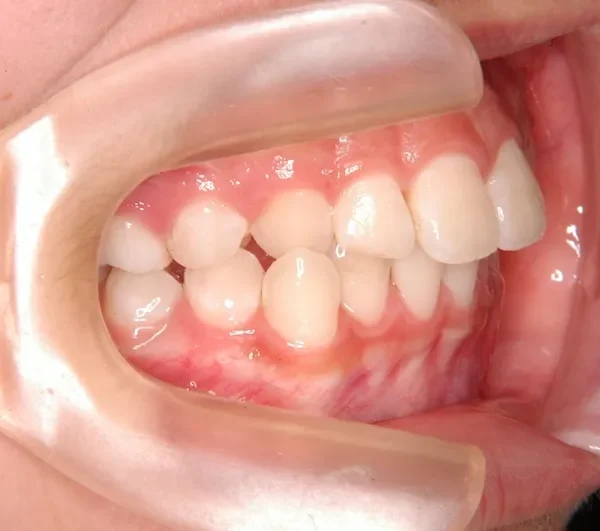

治療経過1

右下の犬歯がずれて生え噛み合わせの邪魔をしています。

歯は抜かず、上下マルチブラケット装置を使用し治療いたしました。

治療回数54回、9年3ヶ月の治療期間で矯正治療を終了しました。

噛み合わせのずれは、ぱっと見綺麗に見えますが、放っておくとのちのち噛みにくくなり、顎関節にまで影響を及ぼしかねません。